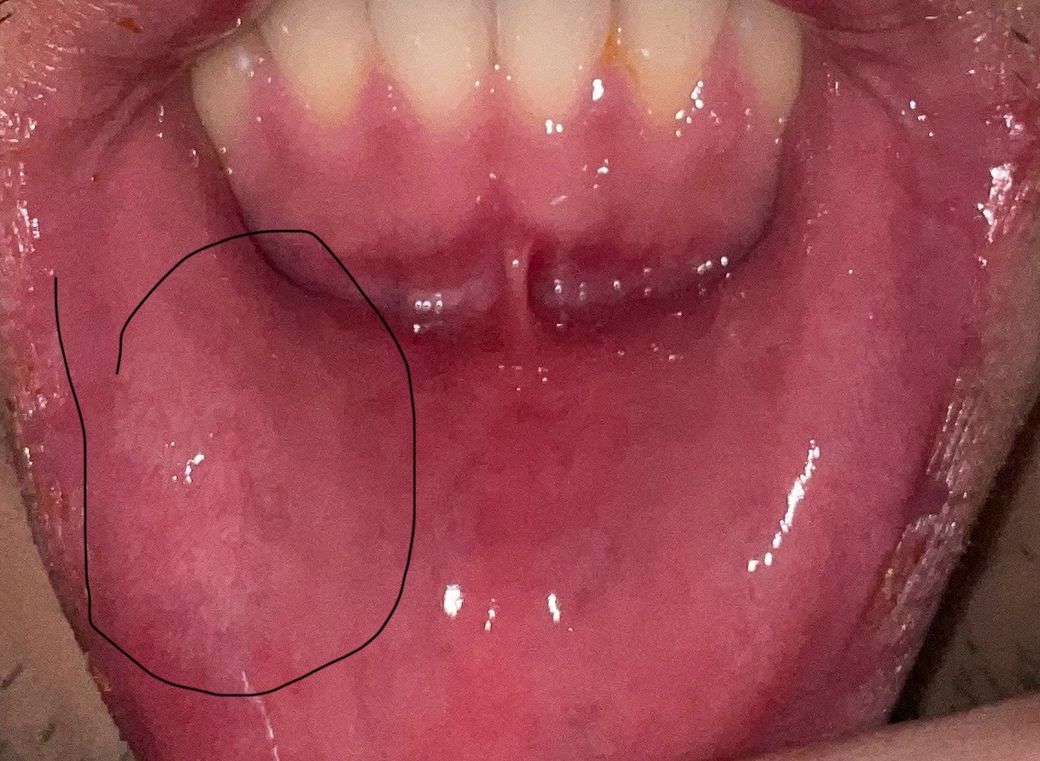

입술에 하얀궤양 두달동안 없어지지 않는데 어떤 질병인가요 구강암인가요?

입술 인쪽에 두달동안 하얀 궤양? 구내염 같은게 없어지지 않고 통증도 있는데 조직검사를 해야하나요 치과에서는 구내염 이라고 히셨는데 두달동안 낫지 않고 점점 커지는 거 같아서요 암인가요? 어떤 질병인가요

일반적으로 젊은 연령과 병변의 형태가 명확하지 않아 구강암의 가능성은 높지 않아 보이나, 병변이 2개월 이상 지속되었다면 추가적인 검사가 필요할 수 있겠습니다. 구강내과 진료를 제공하는 치과의 진료를 받아보시는 것이 좋겠습니다.